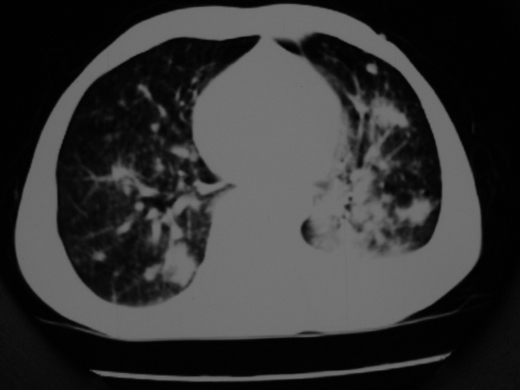

男69岁,年前胸片示肺感染治疗近一月今复查无明显好转,血象正常

双肺内不规则斑点状 片状及结节密实影,部分灶周见索条样影及\"树芽征\",左肺上叶实变,内见充气支气管影及斑状钙化,左侧少量胸腔积液,考虑1)双肺结核2)左侧胸腔积液

右肺多发片絮状结节状及时条索状影,左上肺实变,内可见虫蚀样空洞及支气管气象,左下肺片状及球形病灶,及胸腔积液征象,双肺病灶内多发钙化影,结合病史,考虑双肺继发型肺结核,左胸腔积液

右肺多发片絮状结节状及时条索状影,左上肺实变,内可见虫蚀样空洞及支气管气象,左下肺片状及球形病灶,及胸腔积液征象,双肺病灶内多发钙化影,上纵隔向左侧移位,结合病史,考虑双肺继发型肺结核,左胸腔积液。

右肺多发片絮状、结节状及条索状影,左上肺实变,内可见虫蚀样空洞及支气管气象,左下肺片状及球形病灶,有胸腔积液征象,双肺病灶内多发钙化影,上纵隔向左侧移位,结合病史,考虑双肺继发型肺结核,左胸腔积液。 建议结合ppd检查或纤支镜检查!

右肺可见大片状、云絮状改变。右肺可见散在类圆形影,以外带多见。左肺实变,其内可见明显支气管走行影。纵隔淋巴结有增大,左侧胸腔积液。考虑1、肺结核;2、肺癌肺转移不除外;3、左侧胸腔积液。